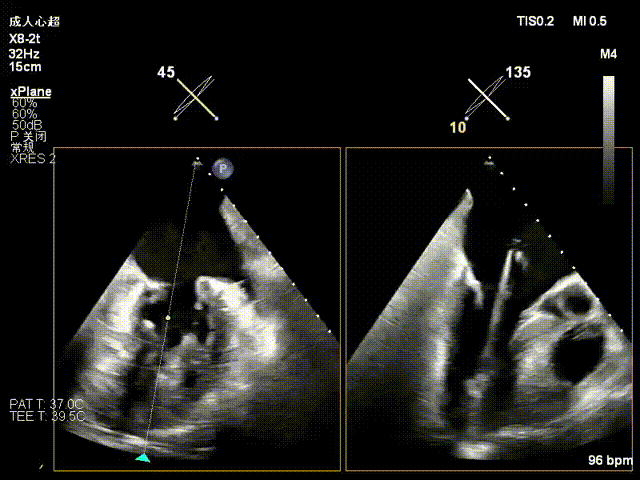

捕获夹合瓣叶1

捕获夹合瓣叶2

收紧夹子并确认夹合效果

评估后解离释放夹子